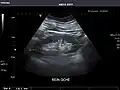

Right kidney -